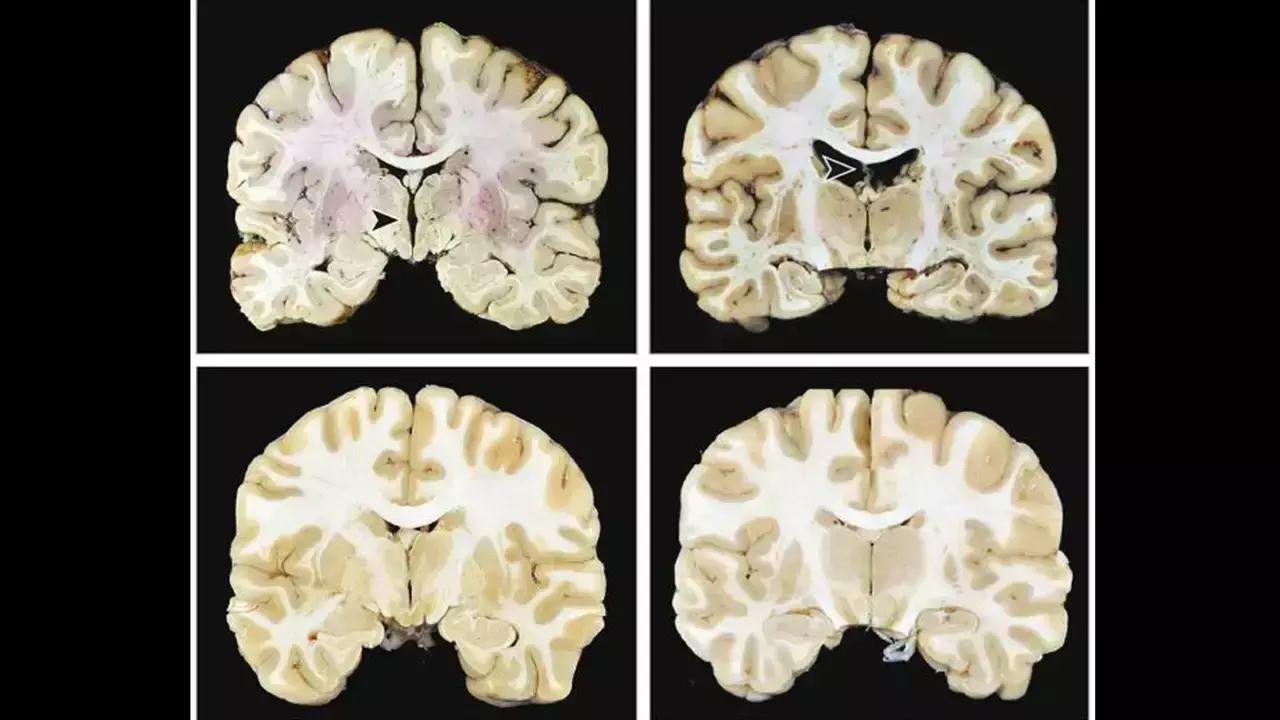

Researchers have found in a large autopsy study of brain donors that without other progressive neurodegenerative diseases, stage III and IV chronic traumatic encephalopathy were associated with significantly higher odds of dementia. In contrast, early-stage (I–II) chronic traumatic encephalopathy showed no association with cognitive symptoms or dementia, indicating that dementia risk rises with advanced chronic traumatic encephalopathy pathology.

This studyexamined the independent contribution of chronic traumatic encephalopathy (CTE) neuropathology to symptoms. The sample included 614 brain donors with (n = 366) and without (n = 248) autopsy-confirmed chronic traumatic encephalopathy. Brain donors with other major neurodegenerative disease diagnoses were excluded. Informants completed cognitive and neuropsychiatric measures. Dementia was determined during diagnostic consensus conferences. chronic traumatic encephalopathy stage IV (of IV) was associated with 4.48 (95% confidence interval [CI] = 1.97–10.90) increased odds of having dementia. chronic traumatic encephalopathy stage III had an odds ratio of 2.12 (95% CI = 1.91–3.77). A higher chronic traumatic encephalopathy stage was associated with greater informant-reported cognitive symptoms (p < 0.01). There were no associations with mood/behavioural scales. Chronic traumatic encephalopathy stage III/IV neuropathology was associated with dementia and cognitive symptoms: those with stage IV were 4.5 times more likely to have dementia than those without chronic traumatic encephalopathy. It is uncertain if low-stage chronic traumatic encephalopathy clinically manifests, and mood/behavioural symptoms likely have multifactorial causes and/or a fluctuating course.